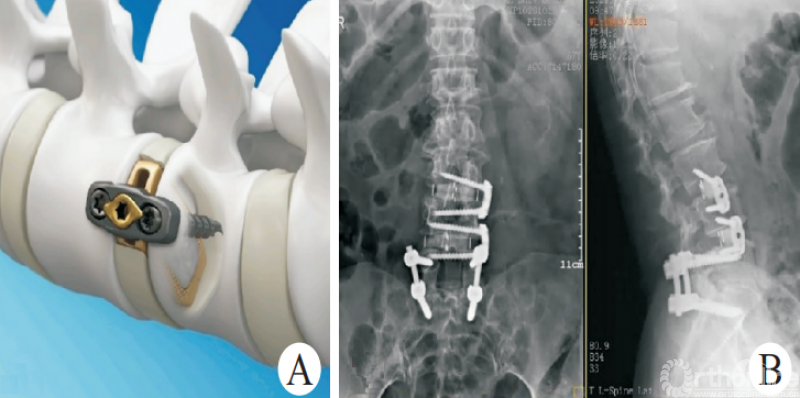

因此,侧方钢板的应用能部分解决这个问题[43]。斜外侧脊柱融合固定系统(PIVOX)(图7)是目前比较成熟的侧方固定方式,已在我科初步应用,用于腰椎节段性不稳定、腰椎椎管狭窄、腰椎侧弯、腰椎盘源性腰痛、邻椎病(图7)等腰椎疾病,截至目前随访结果满意。

图7 PIVOX系统用于邻椎病

初步统计结果显示,相较于经典的OLIF组,PIVOX组并未明显增加融合器沉降、终板塌陷等并发症的发生率。在发挥Stand-alone OLIF优势的同时,保证了脊柱生物力学的稳定性,拓展了Stand-alone OLIF的应用边界。但是,NAYAK等[44]的研究发现,对于侧方脊柱融合术,后路螺钉固定的生物力学稳定性强于侧方钢板固定,因此,当需要刚性、消除运动的稳定时,仍然建议首选后路螺钉固定。